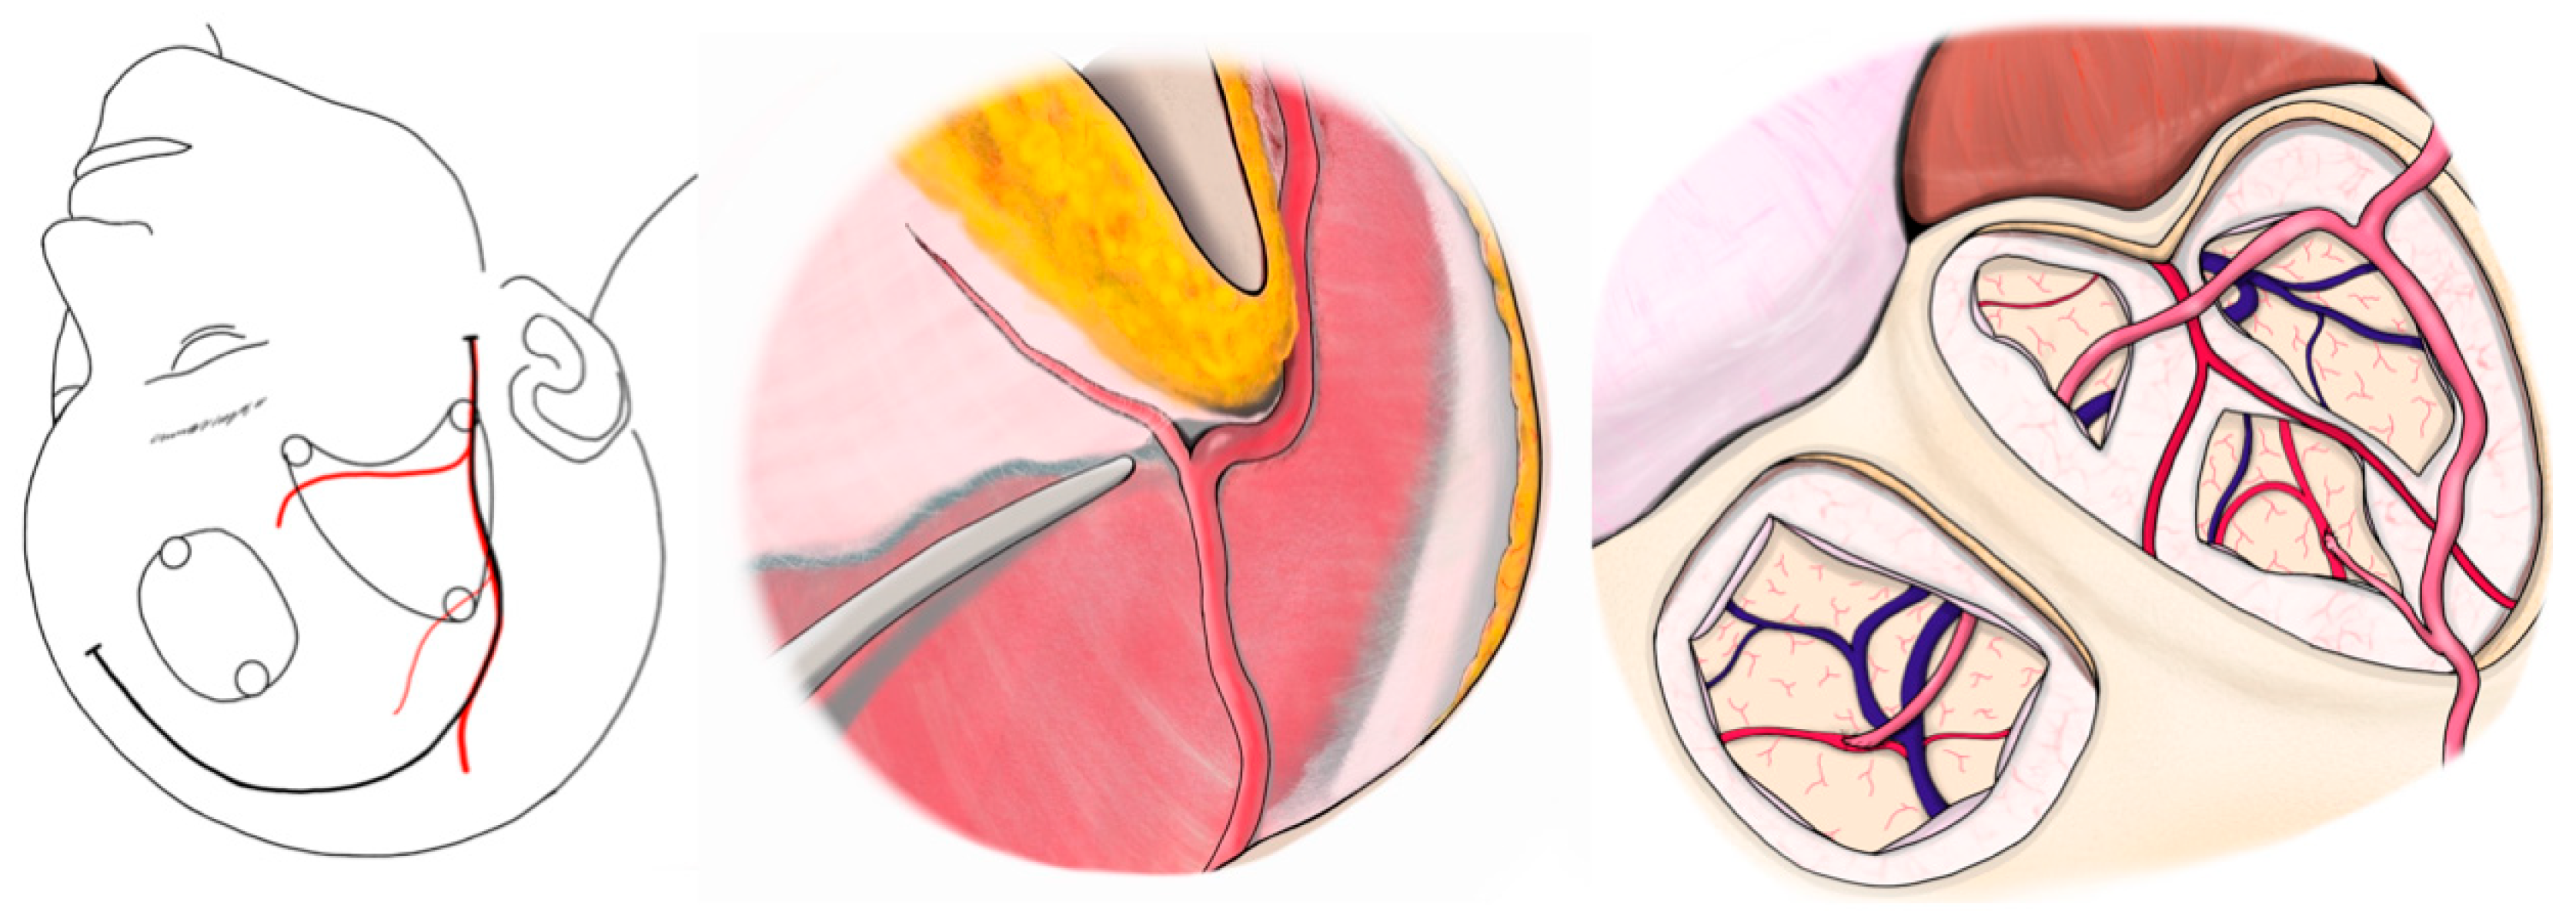

Despite its effectiveness, direct bypass surgery in adult patients with MMD remains challenging. One major concern is that STA donors may not always be optimally suited for anastomosis. The “orthodox” STA-MCA bypass uses one STA branch (frontal or parietal) for a single bypass, or both branches for a double-barrel bypass if broader coverage is needed. However, in some cases, the available cortical recipient artery is very small (diameter < 1 mm), and a larger donor artery can produce a flow surplus and technical difficulty in suturing because of a caliber mismatch. Furthermore, bypass of small recipient vessels is associated with an increased risk of hyperperfusion [3]. Our institutional experience includes cases of cerebral hemorrhage resulting from hyperperfusion following bypass with a significant donor–recipient caliber mismatch (Figure 1). In such situations, conventional bypass using the main STA branch may not be ideal.

Figure 1. Demonstration of a 46-year-old man underwent left-sided revascularization for Moyamoya disease with an ischemic onset. A difference in the caliber was observed between the donor and recipient arteries. The patient was postoperatively managed with sedative intubation due to concerns regarding the risk of hyperperfusion. Immediately after surgery, CT showed extensive cerebral hemorrhage. (A) MRA. Poor delineation of bilateral internal carotid artery endings was observed. (B) DWI. Left acute cerebral infarction was observed (red arrow). (C) STA parietal branch was particularly well developed (red arrow). (D,E) The STA parietal branch trunk (2 mm) was anastomosed to M4 of the frontal lobe (0.9 mm, black circle). (F) Immediately after surgery, extensive cerebral hemorrhage is observed in the left frontal lobe. CT, computed tomography; DWI, diffusion-weighted image; MRA, magnetic resonance angiography; STA, superficial temporal artery.